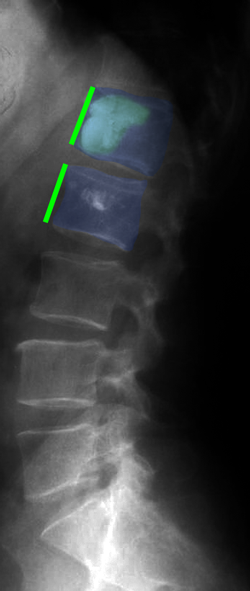

Κάταγμα 01 (φούξια) με μείωση του ύψους του σπονδύλου σε σύγκριση με τον υποκείμενο υγιή σπόνδυλο (μπλέ)(αριστερά). Κυφοπλαστική με ανάταξη του κατάγματος και επαναφορά του ύψους του σπονδύλου στο φυσιολογικό (δεξιά). |